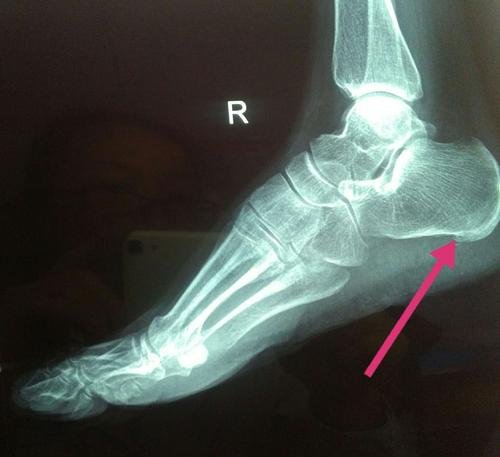

门诊经常遇到患者问这样的问题:我脚后跟疼痛是不是长了骨刺,疼痛跟骨刺有关系吗?患者总认为是骨刺导致了足跟痛,甚至认为“只要骨刺不去除,我的疼痛就不会好”

其实跟骨骨刺只是一种保护机制,足底筋膜炎才是产生疼痛的根本原因。

足底筋膜炎是一种足底的疼痛性慢性无菌性炎症,疼痛位置常位于足底足跟处。医学上又称为跖筋膜炎,是一种比较常见的足痛症。俗称“跟痛症”。